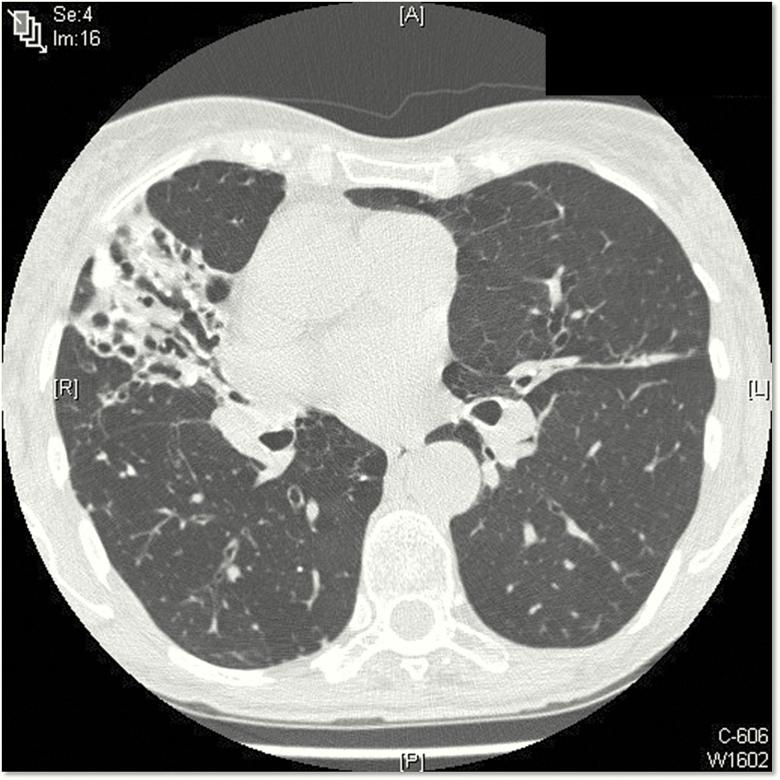

Nontuberculous mycobacteria (NTM) are ubiquitous in the environment and an important cause of disease. The most common species causing pulmonary disease are members of Mycobacterium avium complex (MAC). MAC pulmonary disease (MAC-PD) can be chronic, debilitating, costly, and associated with a high mortality. However, MAC diagnoses are often delayed due to the nonspecific presentation of MAC-PD and radiological findings that overlap with other pulmonary diseases. Patients with risk factors and who meet the diagnostic criteria-which include clinical, radiological, and microbiologic criteria-should be considered for treatment. Diagnosis requires 2 or more positive sputum cultures or 1 bronchoscopic specimen culture. The recommendation for those who are treated is a 3-drug regimen including macrolide, rifamycin, and ethambutol that is continued for 12 months beyond sputum culture conversion to negative. MAC-PD is difficult to treat, with frequent drug-related side effects and suboptimal treatment outcomes. Refractory and recurrent disease is common, leading to lifelong follow-up of patients. There are limited treatment options for patients with macrolide-resistant or refractory disease. Amikacin liposome inhalation suspension is recommended for treatment-refractory patients whose cultures remain positive after 6 months of guideline-based therapy. Among the research priorities to improve patient outcomes and quality of life are developing new, more rapid diagnostic tests, investigating biomarkers associated with disease progression, and identifying new drugs and routes of administration as well as new, shorter, and better-tolerated regimens.

非结核分枝杆菌(NTM)广泛存在于环境中,是疾病的重要病因。引起肺部疾病最常见的物种是鸟分枝杆菌复合群(MAC)的成员。MAC 肺部疾病(MAC-PD)可能是慢性的、使人虚弱的、昂贵的,并与高死亡率相关。然而,由于 MAC-PD 的非特异性表现和与其他肺部疾病重叠的影像学发现,MAC 诊断通常会被延迟。有危险因素且符合诊断标准的患者——包括临床、影像学和微生物学标准——应考虑进行治疗。诊断需要 2 次或以上阳性痰培养或 1 次支气管镜标本培养。对于接受治疗的患者,建议使用包括大环内酯类、利福霉素类和乙胺丁醇在内的 3 种药物方案,在痰培养转为阴性后再继续治疗 12 个月。MAC-PD 难以治疗,药物相关副作用频繁,治疗效果不理想。难治性和复发性疾病很常见,导致患者需要终身随访。对于大环内酯类耐药或难治性疾病的患者,治疗选择有限。对于培养阳性持续 6 个月后仍符合指南治疗的治疗抵抗患者,推荐使用阿米卡星脂质体吸入混悬液。为了改善患者的预后和生活质量,有许多研究重点,包括开发更快速的新诊断测试、研究与疾病进展相关的生物标志物、以及确定新的药物和给药途径,以及新的、更短、耐受性更好的治疗方案。